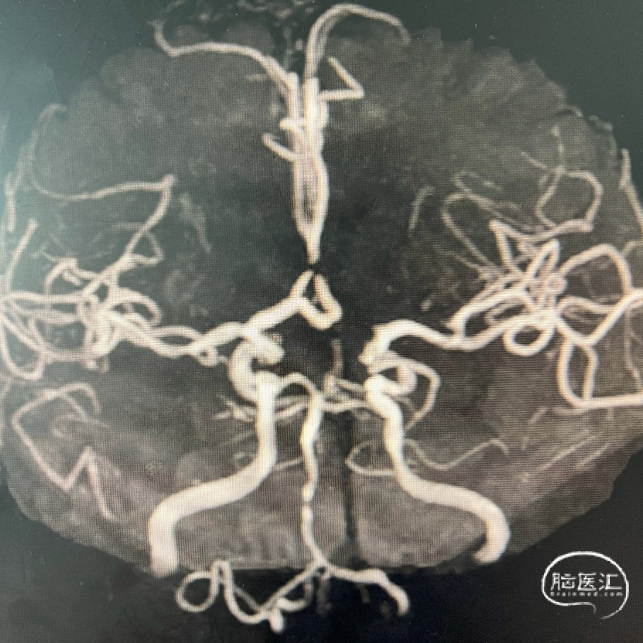

术前MRA

1、主动脉弓及其他弓上血管,III型弓,弓上血管迂曲,血管通畅。

2、颈内动脉系统:

右侧颈总动脉及颈内动脉血管通畅,远端右侧大脑中动脉血流通畅,可见同侧及对侧大脑前动脉显影。

左侧颈总动脉及颈内动脉血流通畅,后交通开放,可见同侧大脑后动脉显影,大脑前动脉血流通畅。

3、椎基底动脉系统:

右侧椎动脉优势型。

左侧椎动脉血管纤细,远端可见基底动脉浅淡显影。

右侧椎动脉优势型,远端汇入基底动脉。

基底动脉中段重度狭窄,狭窄率约80%,双侧大脑后动脉可见显影。